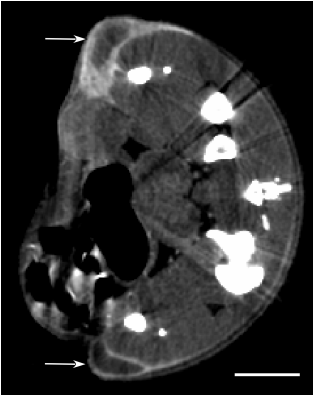

| 腫瘤顯影 | ![]() | 由于AuroVist -15 nm的尺寸較大,因此不會像碘海醇(Omnipaque?;分子量821)。 然而,已經(jīng)證明納米顆粒通過"增強(qiáng)滲透性和保留"(EPR)效應(yīng)離開滲漏的腫瘤新生血管。 金納米顆粒滲入腫瘤并保留在那里,特別是在生長邊緣腫瘤周圍,并在約10 - 24小時內(nèi)積聚。 通過這種機(jī)制,AuroVist -15nm可被腫瘤選擇性吸收。 |